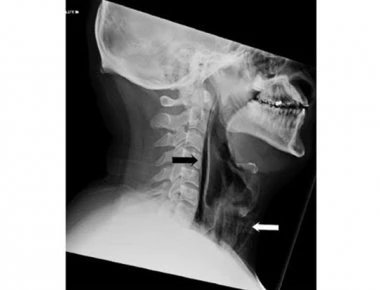

Κράτησε το φτέρνισμά του και τρύπησε ο λαιμός του!

Καταπιέζοντας το φτέρνισμα με το να κρατάμε σφιχτά κλειστά την μύτη και το στόμα μας κινδυνεύουμε να προκαλέσουμε οργανικές βλάβες, προειδοποιούν οι γιατροί και επικαλούνται την περίπτωση ενός 34χρονο...